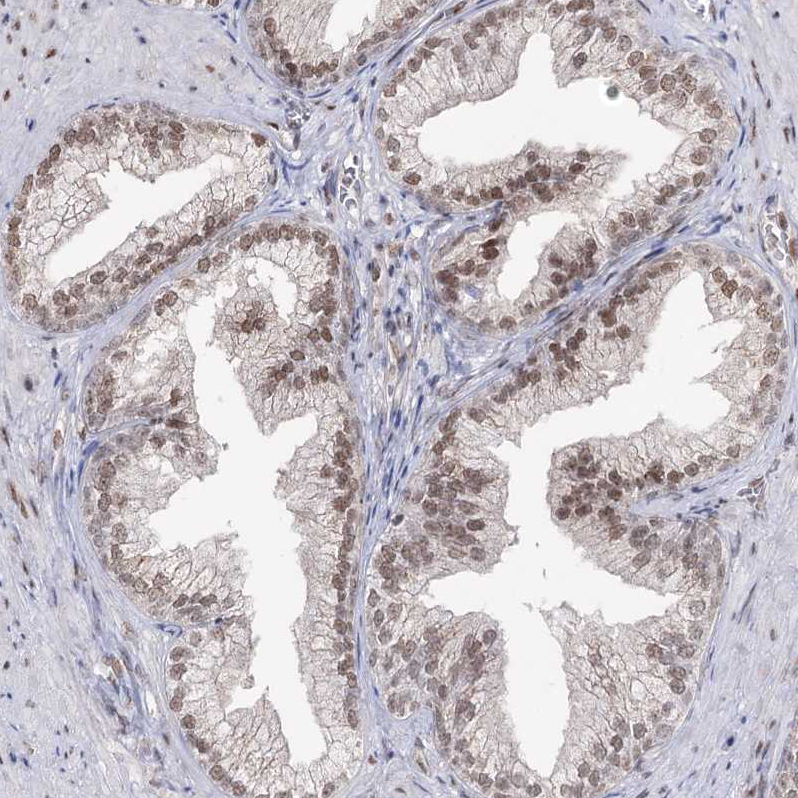

Immunohistochemical staining of human endometrium shows weak nuclear positivity in glandular cells.